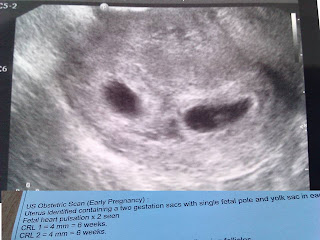

I was so relieved when we saw the pregnancy sack on the screen and saw the tiny heartbeat. I thought I'd be more suprised when the sonographer then showed us the second baby and tiny heartbeat! Twins! We had been praying for both embryos since we knew they existed so it didn't seem that suprising to find out that God had answered our prayers for them. The hospital staff however were suprised by this, UK advice is that only one embryo is replaced at the time both the doctor and embryologist were very happy to replace both, not expecting both to implant and grow!

The grey smudge at the bottom of the black space on the right we were told was the yolk sack and at the very bottom of the grey smudge is the baby. You can't see the second baby in this pic.